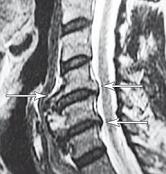

Рентгенограмма № 5

МРТ № 38

На рентгенограмме № 5 шейного отдела позвоночника — выраженный спондилёз третьей степени и остеофитоз, что хорошо видно на МРТ № 38 сегментов шейного отдела позвоночника.